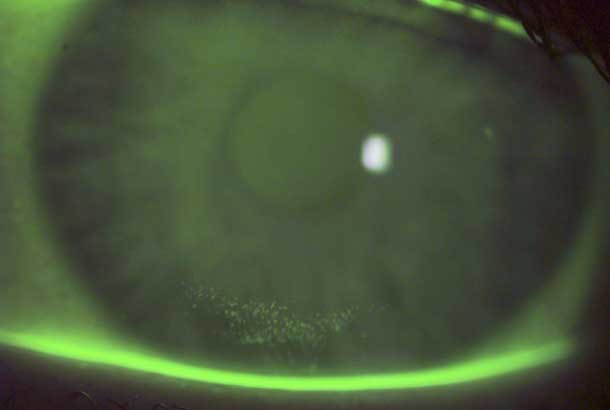

"detail": "<p>Limbal engorgement, limbal redness</p>\n\n<h2>Symptoms</h2>\n\n<ul>\n\t<li>Generally none</li>\n\t<li>May experience mild discomfort</li>\n</ul>\n\n<h2>Signs</h2>\n\n<ul>\n\t<li>Vessel engorgement in limbal region</li>\n</ul>\n\n<h2>Etiology</h2>\n\n<ul>\n\t<li>Association with hypoxia in low Dk/t soft lens wearers</li>\n\t<li>Other inflammatory, chemical, osmotic, physical or irritating stimuli can also produce limbal hyperemia</li>\n</ul>\n\n<h2>Prevalence</h2>\n\n<ul>\n\t<li>Common. Severe forms are rare</li>\n</ul>\n\n<h2>Differential Diagnosis</h2>\n\n<ul>\n\t<li><a href=\"/condition/39\">Vascularization of the cornea</a>&nbsp;(i.e, new vessel growth)</li>\n\t<li>Vascularized limbal keratitis</li>\n\t<li>Superior limbal keratoconjunctivitis</li>\n\t<li>Uveitis</li>\n\t<li>Acute glaucoma</li>\n\t<li>Keratitis</li>\n\t<li><a href=\"/condition/63\">See: Hyperemia and Vascularization &ndash; Differential Diagnosis</a></li>\n</ul>\n\n<h2>Management</h2>\n\n<ul>\n\t<li>Improve peripheral corneal oxygenation (e.g, refit with SiHy lens)</li>\n\t<li>Reduce wearing time if previously wearing excessively</li>\n\t<li>Failure to remove the stimulus may lead to vascularization of the cornea</li>\n</ul>",

"images": [